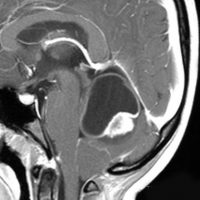

5. 後交連 PC posterior commissure

松果体腫瘍が上丘を圧迫して眼球運動障害を呈することは良く知られています。実際に松果体腫瘍の手術で上丘を損傷することはほとんどなく,術後に残る微妙な複視は,後交連 (PC posterior commissure) の損傷によって生じます。左の画像のように,松果体腫瘍が第3脳室方向に伸展増大すると後交連を圧排して,後交連は扁平化します。手術中には,上丘の奥に,上丘と連続して白く薄い脆弱な白質組織が見えます。それが後交連です。左右にも長い白質組織なので,腫瘍底面から非常に慎重に剥離する必要があります。後交連の剥離が終わると第3脳室内の髄液腔に抜けます。

左の図は,眼球運動に関わる中枢と神経を表したものですが,PTAの手術で損傷するのは,PC 後交連とSC 上丘くらいなもので,上丘は丈夫な組織なので,術後合併症である複視は後交連損傷であることが多いのです。